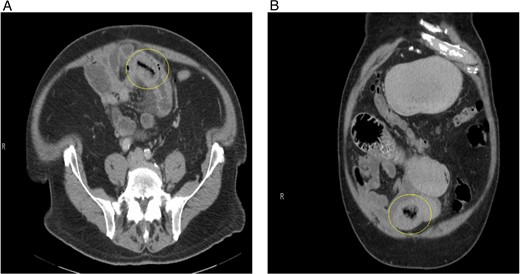

A 77-year-old male with a medical history of hyperlipidemia presented to the emergency department (ED) with diffuse lower abdominal pain. Physical examination revealed mild tenderness in the lower left quadrant. Computed tomography (CT) of the abdomen with oral contrast revealed an abnormally thickened small intestinal loop with possible intussusception causing low-grade partial obstruction (Fig. 1). Due to increasing abdominal pain, the patient underwent diagnostic laparoscopy, and a narrowed segment of the small bowel was found. Intussusception was not seen, the scarred and narrowed segments were resected, and primary stapled anastomosis was performed. The distal collapsed bowel was examined 2 feet from the transition point, and no lesions or masses were observed. The pathology of the resected bowel segment was benign.

(A) Initial CT abdomen (transverse view) revealing what was thought to be intussusception but turns out to be primary enterolith with an air filled core. (B) Initial CT abdomen (coronal view) revealing what was thought to be intussusception but turns out to be primary enterolith with an air filled core.